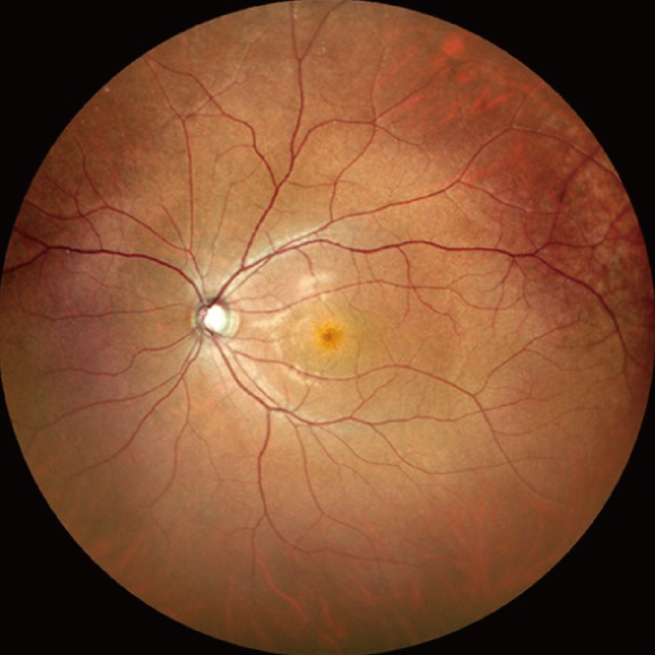

共焦点走査型ダイオードレーザ検眼鏡 Mirante

Miranteは眼底検査用の微弱なレーザ光を用いて撮影する「SLO」と、SLD 光源を用いて撮影する「OCT」の両方を組み合わせ、高画質・高精細に眼底撮影をおこなう装置です。

MiranteのSLO検査では、赤・緑・青の3色のレーザ光を使って撮影することにより、1670万画素(4096×4096 ピクセル)のカラーSLO撮影をおこなえます。また、オプションの広角アダプタを取り付けることにより、標準画角で対角60°からΦ110°まで撮影範囲を拡げることができます。